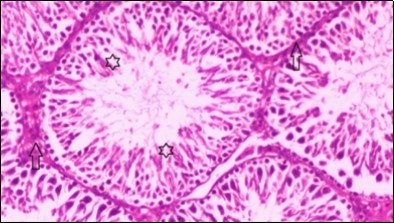

Figure 3.Photomicrogragh of testis section of a control rat showing testicular tissue with seminiferous tubules separated by interstitial tissue with Ledying cells (arrow). Seminiferous tubules with complete spermatogenesis, Sertoli cell (dashed-arrow) and spermatozoa . (H&E) (40X).

Photomicrogragh of testis section of a control rat showing testicular tissue with seminiferous tubules separated by interstitial tissue with Ledying cells (arrow). Seminiferous tubules with complete spermatogenesis, Sertoli cell (dashed-arrow) and spermatozoa . (H&E) (40X).